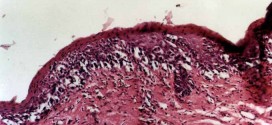

Leer MásMETÁSTASIS CUTÁNEAS

Las metástasis cutáneas. Durante los primeros años de vida de una persona, las células normales se dividen más rápidamente para permitir el crecimiento. El cuerpo está compuesto por billones de células vivas. Las células normales del cuerpo crecen, se dividen formando nuevas células y mueren de manera ordenada. Una vez que se llega a la edad adulta, la mayoría de …